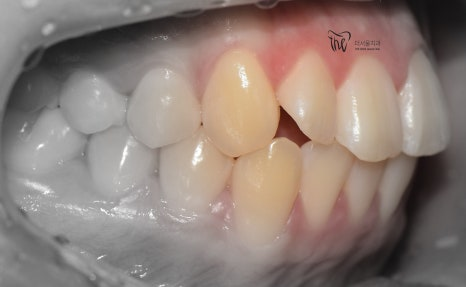

부정교합 2급 이라는 것은, 하악보다 상악이 더 전방에 위치되거나 또는 상악의 치아들이, 하악 치아들보다 더 앞쪽에 위치되어 있는것을 뜻하며

증세를 갖고 계셨던 분의 임상 증례를 보여드립니다. 교정 치료를 통해서 2급 부정교합이 개선 되었으며 치료를 끝으로, 턱 끝에 보형물